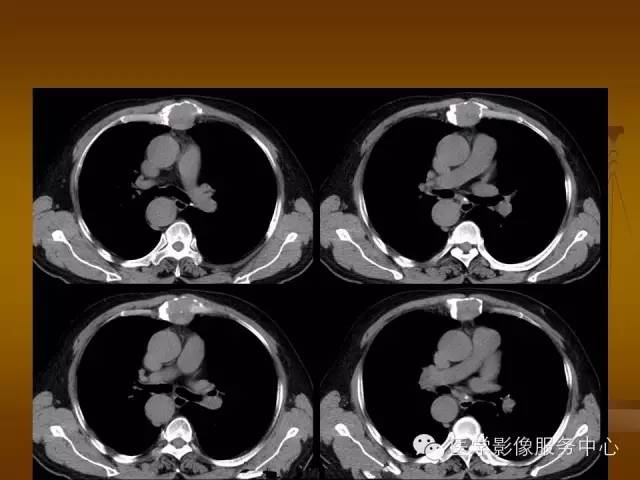

胸骨浆细胞骨髓瘤1例CT影像表现

骨质破坏区完全为软组织取代,骨质膨胀,边界清楚,常突破骨皮质形成软组织肿块。

增强扫描可见病灶轻中度强化,一般于静脉期达峰值。